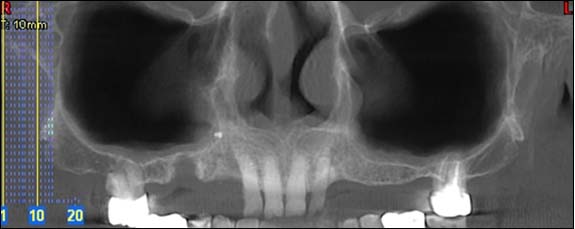

Reconstruction panoramique